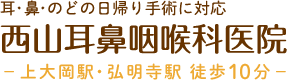

鼻茸、鼻ポリープとは

鼻茸は、慢性副鼻腔炎と併発する症状の1つです。鼻にできるポリープであり、鼻の中の粘膜に白く膨れあがった塊ができますが、悪化すると鼻の穴から見えるほど大きくなる場合もあります。

鼻茸は、慢性副鼻腔炎と併発する症状の1つです。鼻にできるポリープであり、鼻の中の粘膜に白く膨れあがった塊ができますが、悪化すると鼻の穴から見えるほど大きくなる場合もあります。

鼻茸ができると鼻の気道を塞いでしまいますので、鼻づまり、嗅覚障害、頭痛の原因となるほか、鼻から呼吸しにくくなって口呼吸となるためさまざまな悪影響の可能性がでてきます。

鼻茸は薬で小さくすることはできますが完治することは難しいため、手術が必要となります。当院では日帰り手術で鼻茸の切除治療を行っています。

4鼻茸(はなたけ)とはなんですか?

慢性副鼻腔炎で、鼻の粘膜が水ぶくれのように膨らんだ状態になったり、鼻ポリープができることがあります。それを鼻茸と呼びます。

手術が必要とされるのは、薬の治療で効果が見られない場合や、鼻茸が見られる場合です。内視鏡下副鼻腔手術では、細い内視鏡を鼻腔に挿入して鼻茸の切除や患部を処置します。他に、経上顎洞的副鼻腔手術という上の唇と歯茎の間を切り開いて中にある粘膜を取り除く手術もありますが、内視鏡手術は痛みや腫れが大幅に抑えられますし、回復も早いため近年ではほとんどが内視鏡手術となっています。手術所要時間は1~2時間程度であり、ほとんどの場合、日帰りで受けることができます。鼻茸は一度できてしまうと手術で切除しても必ず再発します。